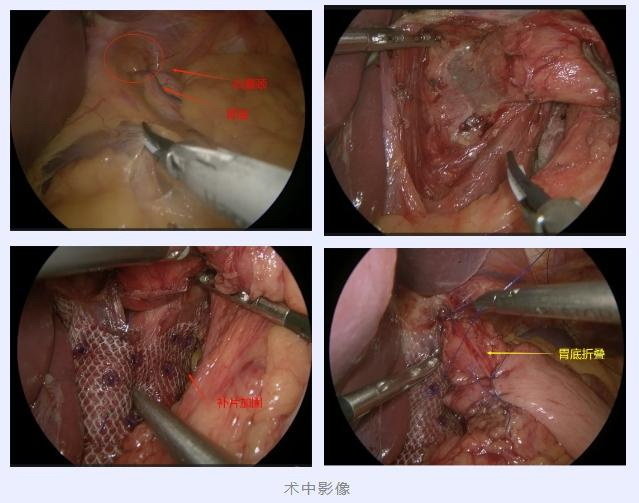

找到了原因,翟博教授随即为刘大爷安排了手术治疗,拟定手术方案为“腹腔镜下食管裂孔疝修补术+胃底折叠术”。术中见胃底由扩大的食管裂孔疝入胸腔,还纳疝内容物后,关闭扩大的食管裂孔疝,为加强胃食管抗反流屏障作用,又以胃底包绕食管进行胃底折叠。

所有的操作都通过腹腔镜微创完成,整个手术完成后肚子上仅有几个不到1cm的小孔。